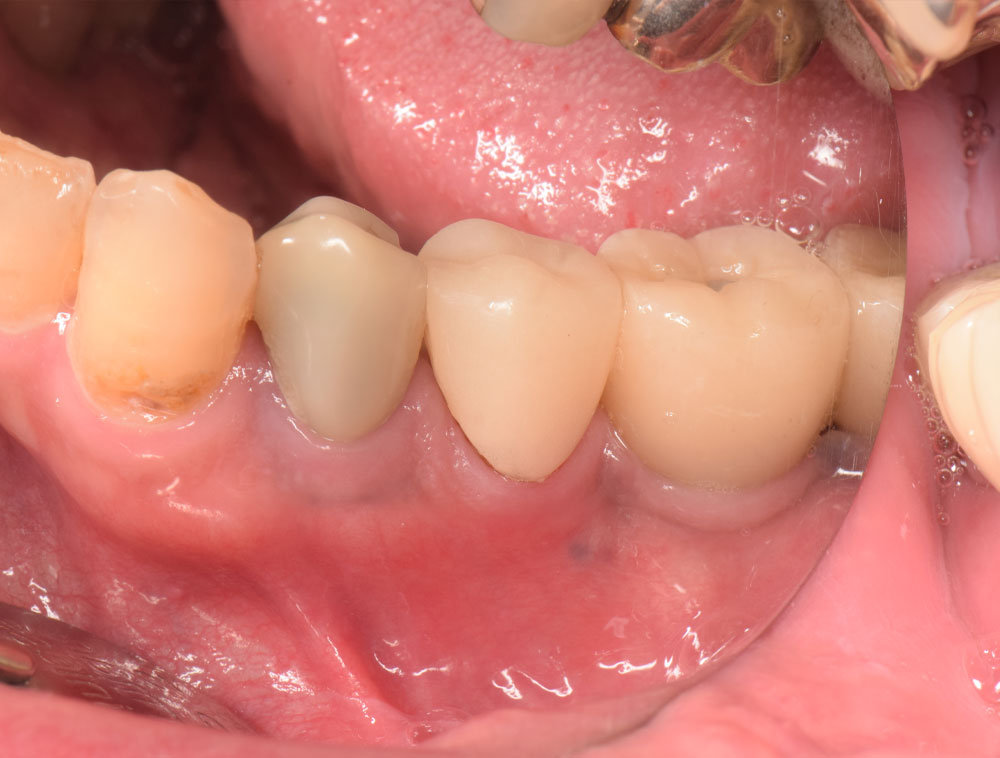

治療前

患者さんは50代の男性で、顎を動かして話したり食べたりする際、奥歯に過度の力や加わり、また上下の歯同士がぶつかることで、歯に負担がかかりその1本の歯だけでなく周囲の歯にも影響を及ぼしていました。そのため他医院で保険による銀歯の被せ物の治療を繰り返されていらっしゃったとのこです。今回は下顎の銀歯を白いセラミックで綺麗にしたいということで、恵比寿・広尾歯科に来院されました。お口のなかを拝見すると本来は顎が左右に動く際には犬歯が起点となって、奥歯に強い横向きの力が加わらないように隙間をつくるのですが、この患者さんは犬歯の働きが正しくできずに奥歯に強い力が加わり続けていました。この強い噛み合わせは歯周病の要因(咬合性外傷)となったり、周囲の歯をふくみ欠け・割れを引き起こすことがあります。根本原因を解決せずに白いセラミックで治療しても、固いセラミックにより反対側の歯を痛めてしまったり、時には固いセラミックも欠けるようなダメージを歯に受けることもあります。そこで根本的な噛み合わせと顎運動の改善から治療をスタートし、仮歯で時間をかけて患者さんの理想的な犬歯誘導が行われる形態と噛み合わせをつくり、最終的にセラミックの本歯で治療を終えました。